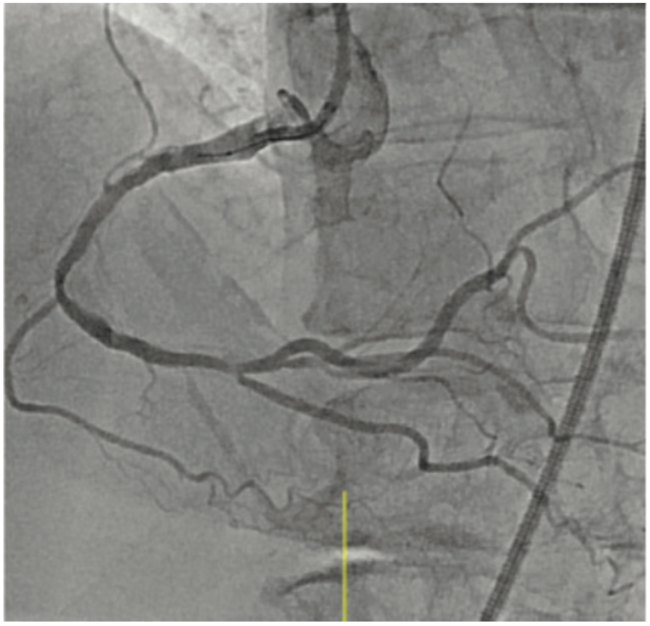

Intravascular lithotripsy (IVL) has been shown to be both safe and effective in the treatment of calcified coronary artery disease, with low rates of device-related adverse events, as shown in the DISRUPT CAD study series.3-6 Certainly, any device that may assuage operator concerns regarding complications when treating complex lesions could translate to an increase in use of calcium modification where indicated. Since we know that inadequate lesion preparation may lead to higher rates of in-stent restenosis and stent thrombosis, it follows that IVL could help lower suboptimal PCI rates in both men and women.

Small retrospective studies have suggested that women may be at an increased risk for procedural complications after atherectomy. Procedural complications are often related to vascular injury during plaque modification. As post-menopausal women have been shown to have increased arterial stiffness, less vessel compliance, and increased vascular fragility, it is not surprising that these factors, in conjunction with smaller coronary artery size, could lead to higher rates of coronary perforation and dissection during treatment of calcified plaque. The sex-specific analysis of the DISRUPT CAD series of studies presented at SCAI 2022 demonstrated that there was no difference in angiographic complications, successful stent delivery, and 30-day adverse cardiovascular events between men and women.7 These are certainly reassuring data, which suggest that the possible safety signals seen in women treated with atherectomy may not be present with IVL.